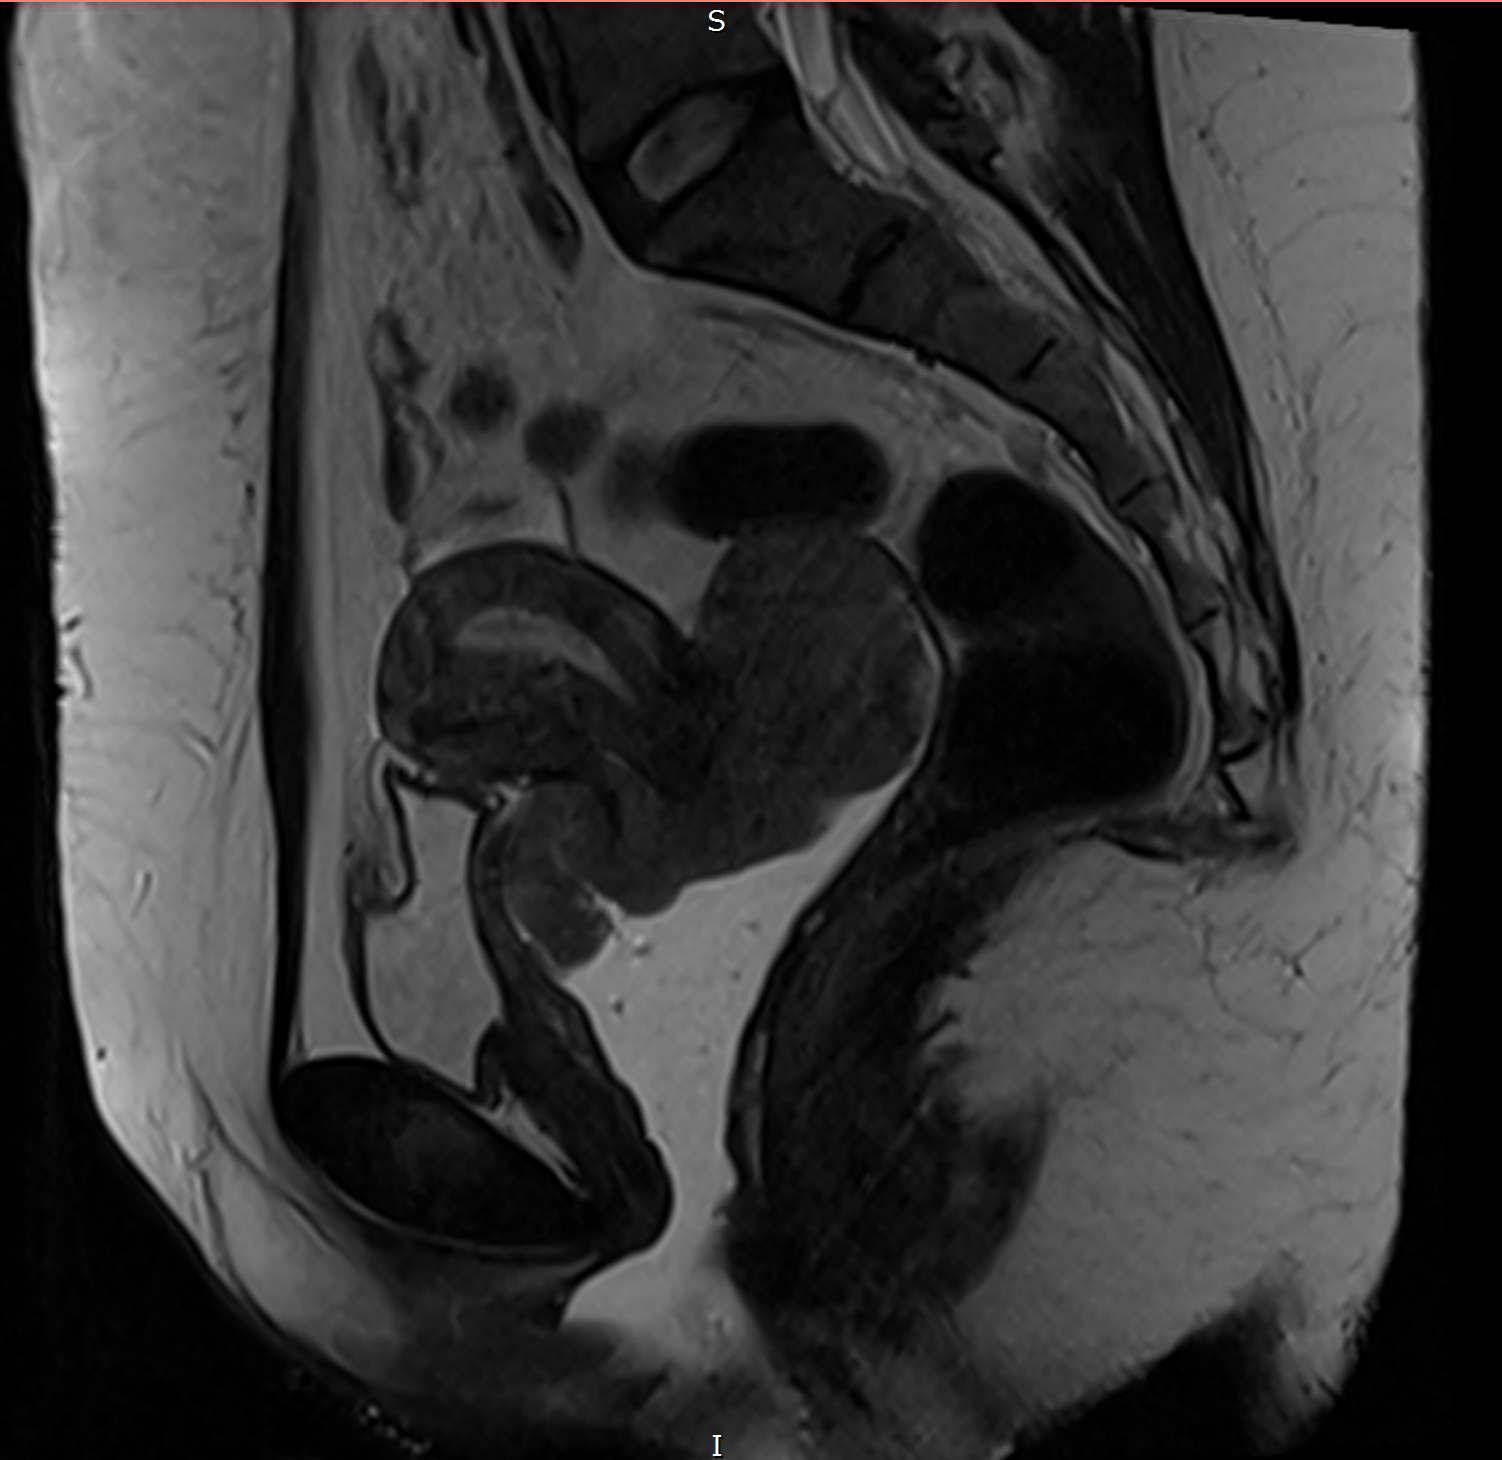

acretismo_RM

Versão completa (explicativa) Ressonância magnética da pelve (plano sagital, sequência ponderada em T2). Observa-se placenta prévia centro-total, com sinal heterogêneo e perda do afilamento habitual, determinando abaulamento do contorno uterino anterior. Notam-se bandas intraplacentárias hipointensas em T2, associadas à irregularidade e adelgaçamento da interface miométrio-placentária, com áreas de perda dessa interface. Achados compatíveis com espectro de placenta acreta.